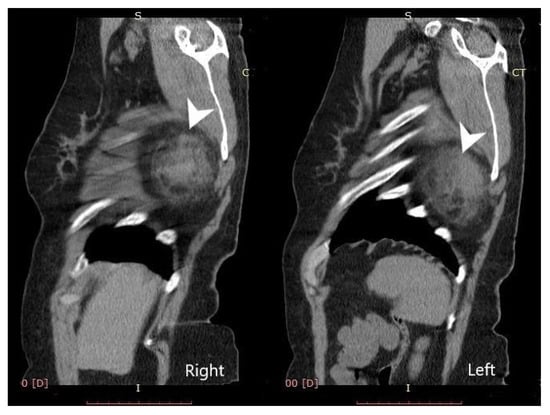

2. Case Presentation